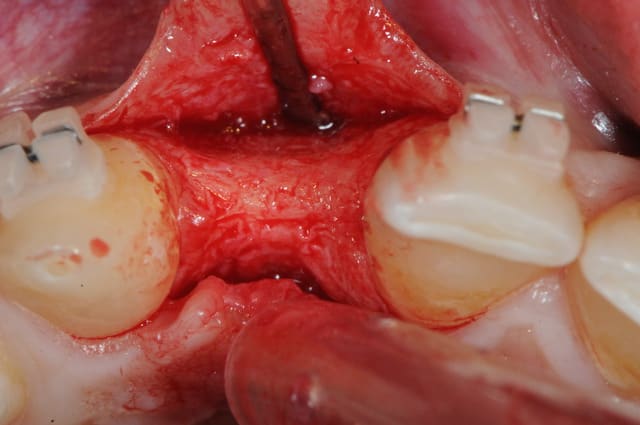

ou comme ça encore...

( agénésie de 12 - expansion osseuse sur une crête fine ) agénésie...

la suite à Sallanches les 2 et 3 Février pour ceux qui veulent encore s’inscrire)

très beau!

joli bombé vestibulaire, il va falloir que je fasse fort pour rester devant!